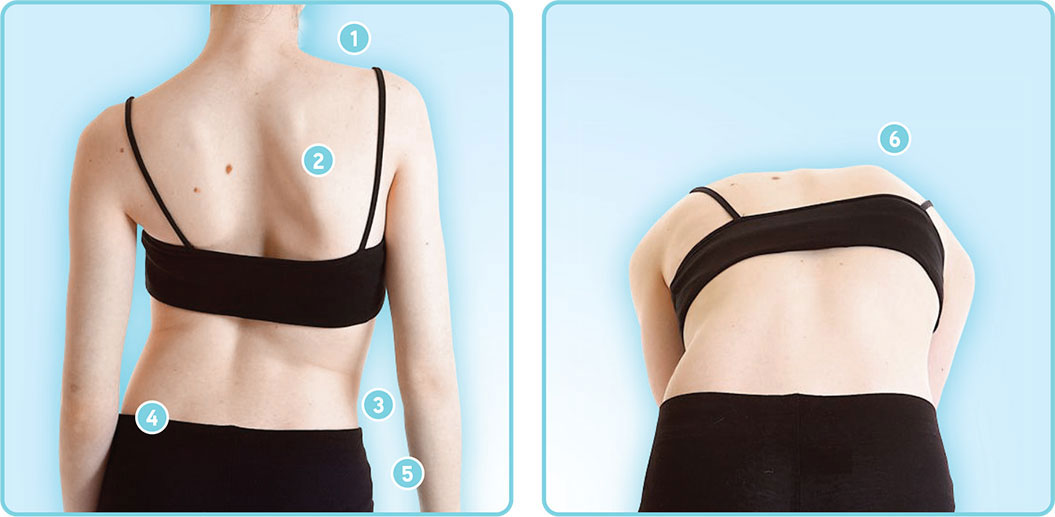

ميل واضح في الكتفين أو الحوض أثناء الوقوف.

يميل الحوض تدريجيًا نحو الأعلى في جهة، وإلى الأسفل في الجهة المقابلة.

ينحني العمود الفقري جانبيًا ليحافظ على توازن الجسم.

في بعض الحالات، ينصح الطبيب باستخدام أو حزام اعوجاج العمود الفقري للحفاظ على استقامة العمود الفقري أثناء فترة العلاج.